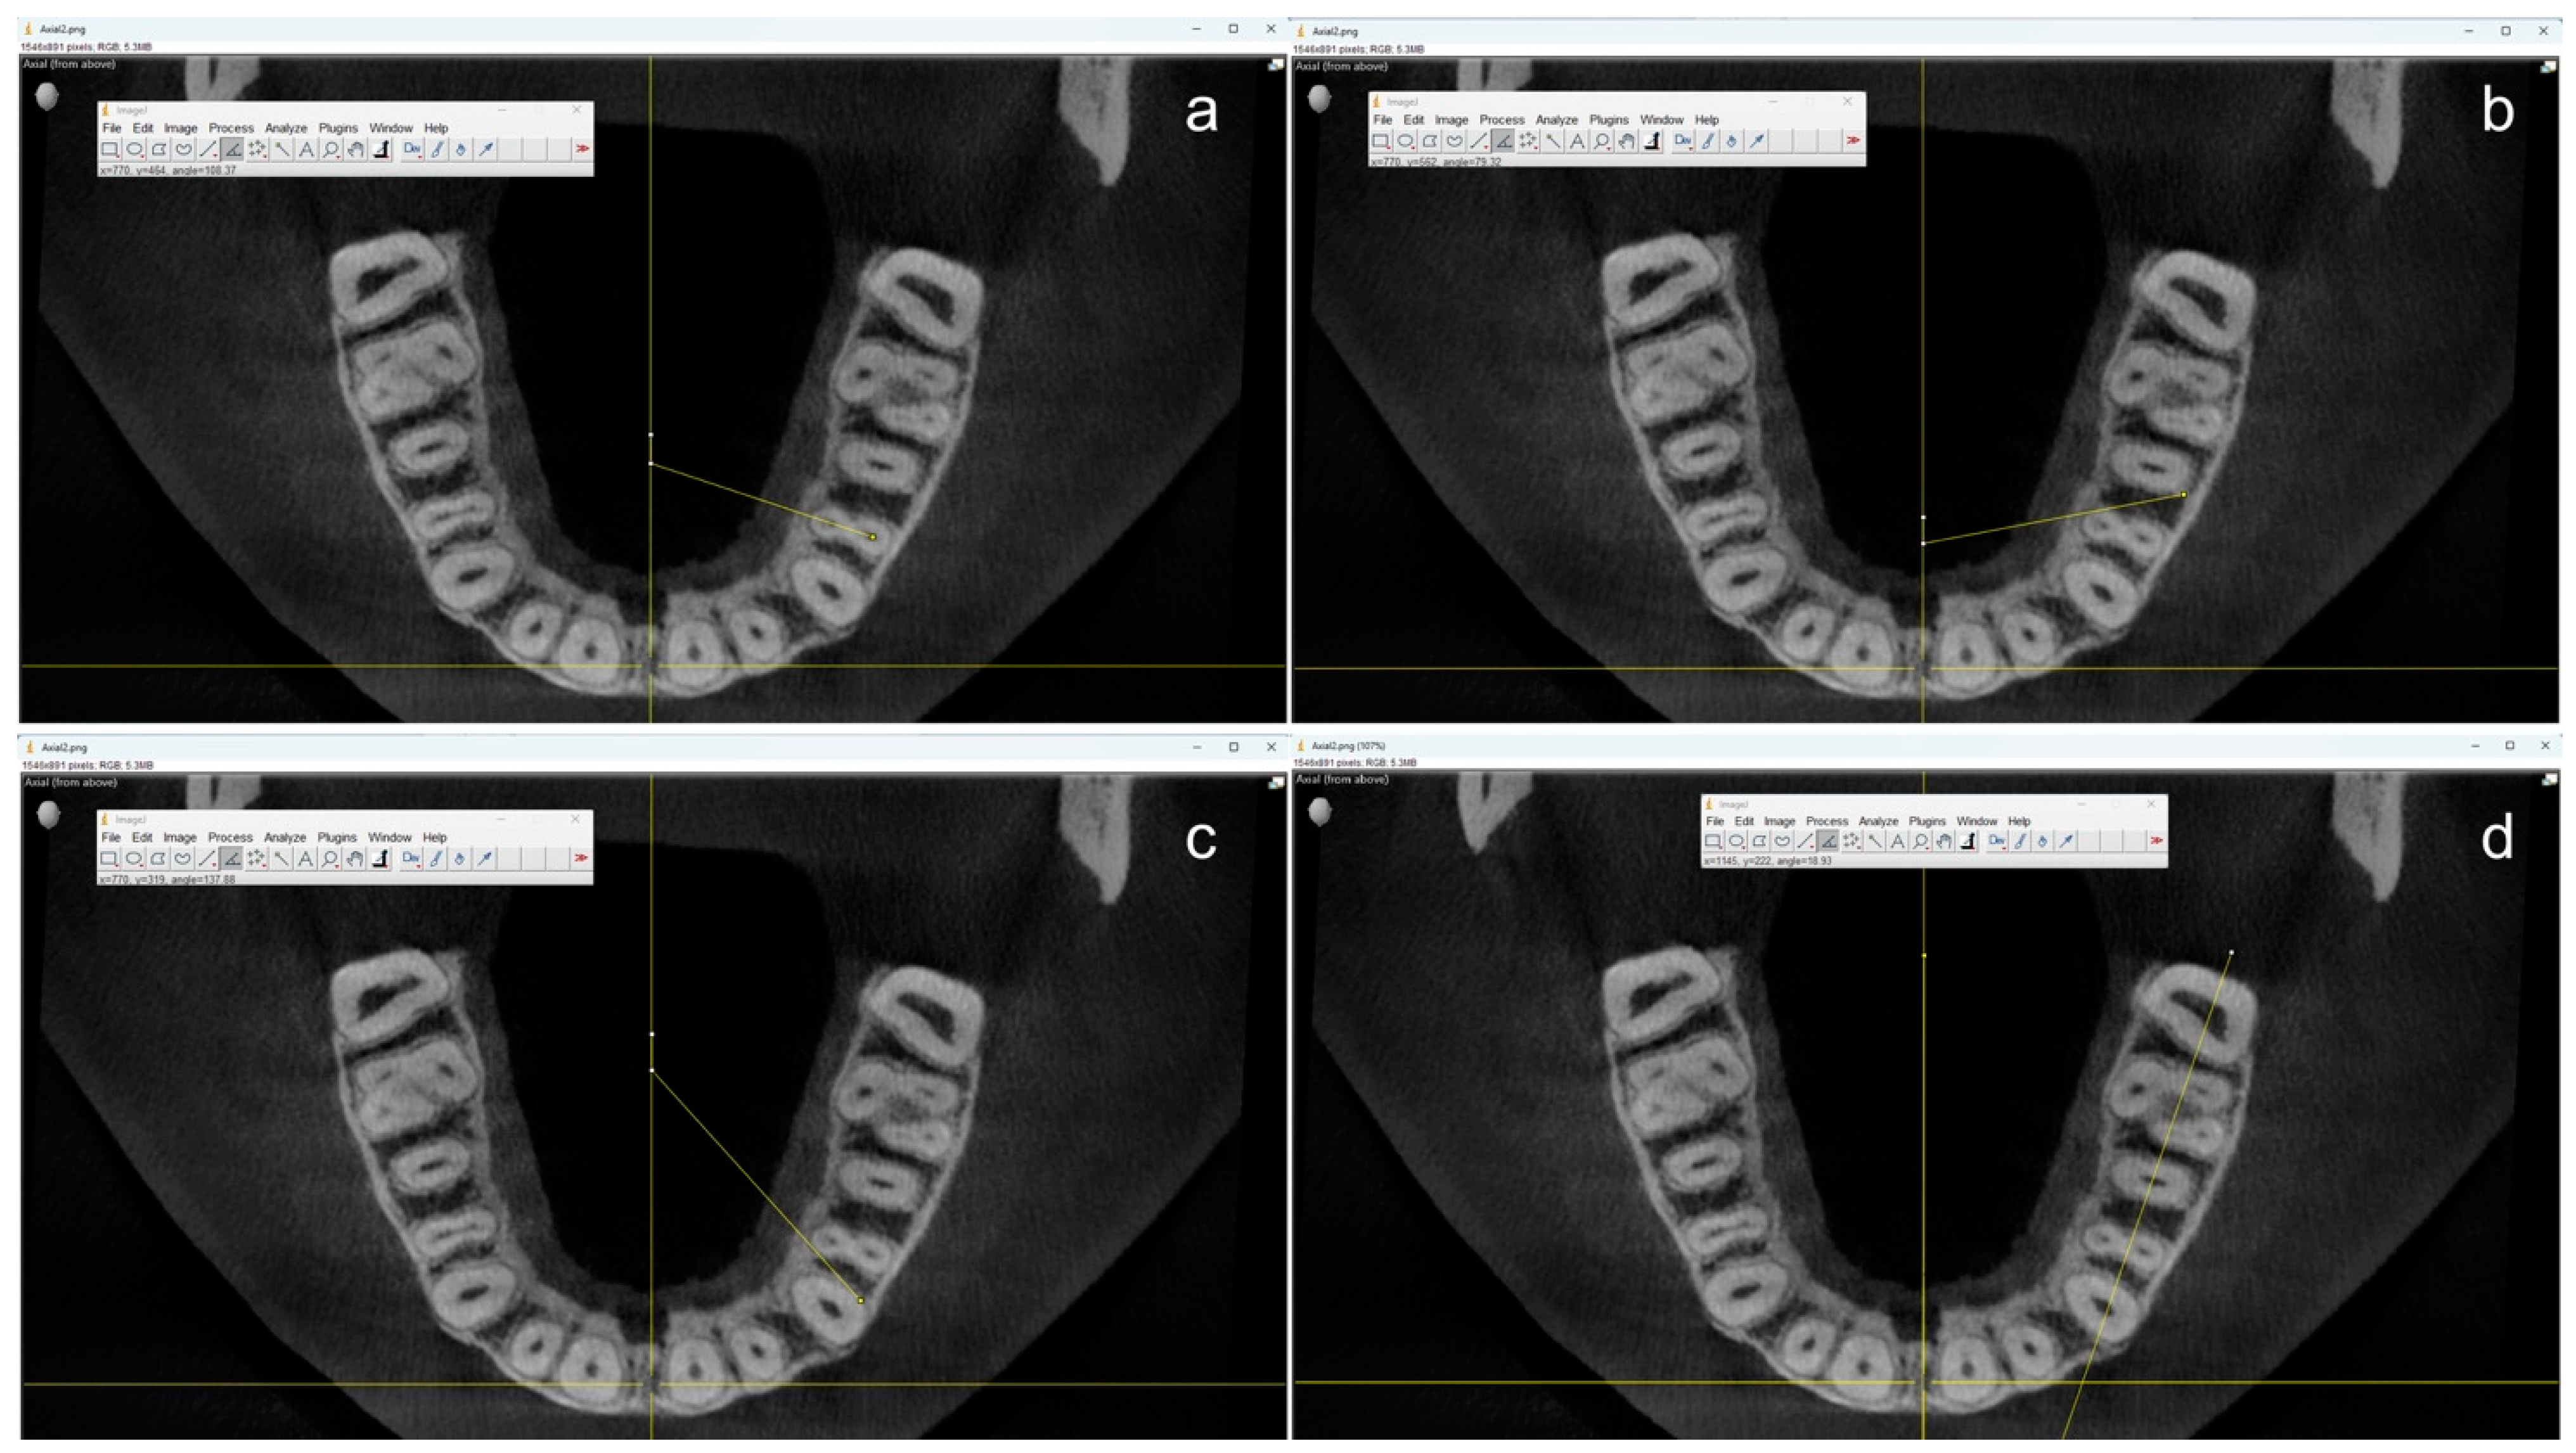

All measurements were performed by one single operator using the open-source software ImageJ (OpenSource, Version 1.54f) starting from the centerline to ensure a uniform reference position (Figure 2).

Figure 2.

Example of measurements in coronal axial planes using ImageJ. The angle through the root canal(s) (a) and the angles where the neighboring teeth would start to overlap the first premolar from the distal (b) and the mesial (c) were measured using the center of the maxilla as a reference. Additionally, the angle between the jaw and the central axis (d) was measured for final calculations.

First, the angle at which the two root canals of the maxillary first premolars overlap was measured by drawing a line through the center of these canals. Two additional angles were measured to determine the angle at which the neighboring teeth would start to overlap the first premolar. On the one hand, the angle between the distal contour of the adjoining canine and the mesiopalatal contour of the first premolar. On the other hand, the angle between the distal root contour of the first premolar and the mesial root contour of the second premolar. If a root canal was not clearly visible in the apical section, the center of the root contour was used as an orientation aid. Teeth with root canal fillings, root resorptions, atypical anatomy (e.g., more than two roots), and CBCT artifacts to the extent that made valid measurements impossible were not taken into account for this study.

Because it can be assumed that an IO X-ray film or sensor is usually placed parallel to the jaw and not at the center of the palate, the angle between the jaw and the central was additionally measured, and the respective angles were calculated accordingly.